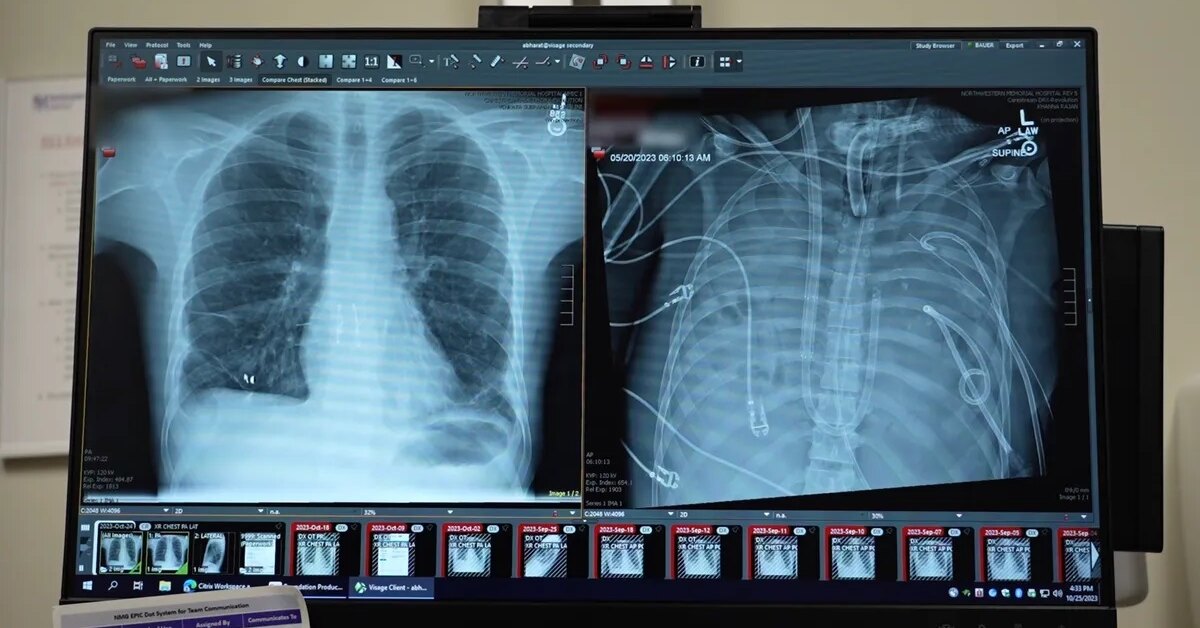

В новой статье, опубликованной в журнале Med, ученые описали случай 33-летнего мужчины, у которого развился острый респираторный дистресс-синдром из-за тяжелого гриппа. Ситуацию осложнила бактериальная инфекция, вызвавшая разрушительную пневмонию. Легкие перестали выполнять свою функцию, а затем начали отказывать сердце и почки. Стандартная терапия уже не помогала.

Обычная пересадка была слишком рискованной – организм был истощен инфекцией. Тогда врачи пошли на крайний шаг: полностью удалили пораженные легкие, чтобы остановить распространение инфекции. Возникла главная проблема – как поддерживать жизнь без органа, который отвечает за насыщение крови кислородом.

Команда создала систему полной искусственной замены легких (total artificial lung, или TAL). Кровь отводилась из правых отделов сердца, проходила через внешний контур, где удалялся углекислый газ и добавлялся кислород, а затем возвращалась в левое предсердие. При этом система регулировала давление и поток крови, чтобы сердце продолжало работать стабильно. В отличие от стандартных аппаратов ЭКМО, эта схема полностью брала на себя функции легких.